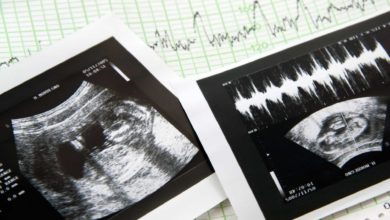

Senado do Alabama aprova lei anti-aborto mais severa dos EUA

O Senado do estado norte-americano do Alabama acaba de votar uma lei que passa a proibir o aborto em quase todas…